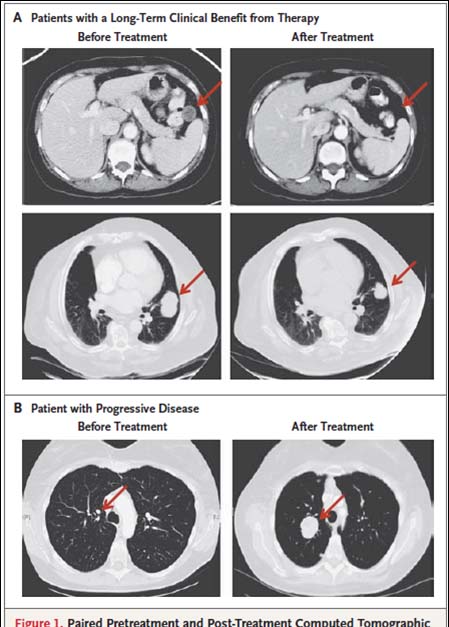

A:有效 B:无效

肿瘤突变多—T细胞多—治疗有效